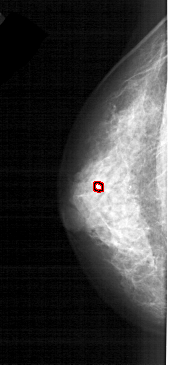

FILE: A_1609_1.LEFT_MLO.OVERLAY

TOTAL_ABNORMALITIES 1

ABNORMALITY 1

LESION_TYPE CALCIFICATION TYPE PLEOMORPHIC DISTRIBUTION CLUSTERED

ASSESSMENT 4

SUBTLETY 2

PATHOLOGY BENIGN

TOTAL_OUTLINES 1

LEFT_MLO LINES 5191 PIXELS_PER_LINE 2056 BITS_PER_PIXEL 12 RESOLUTION 43.5 OVERLAY